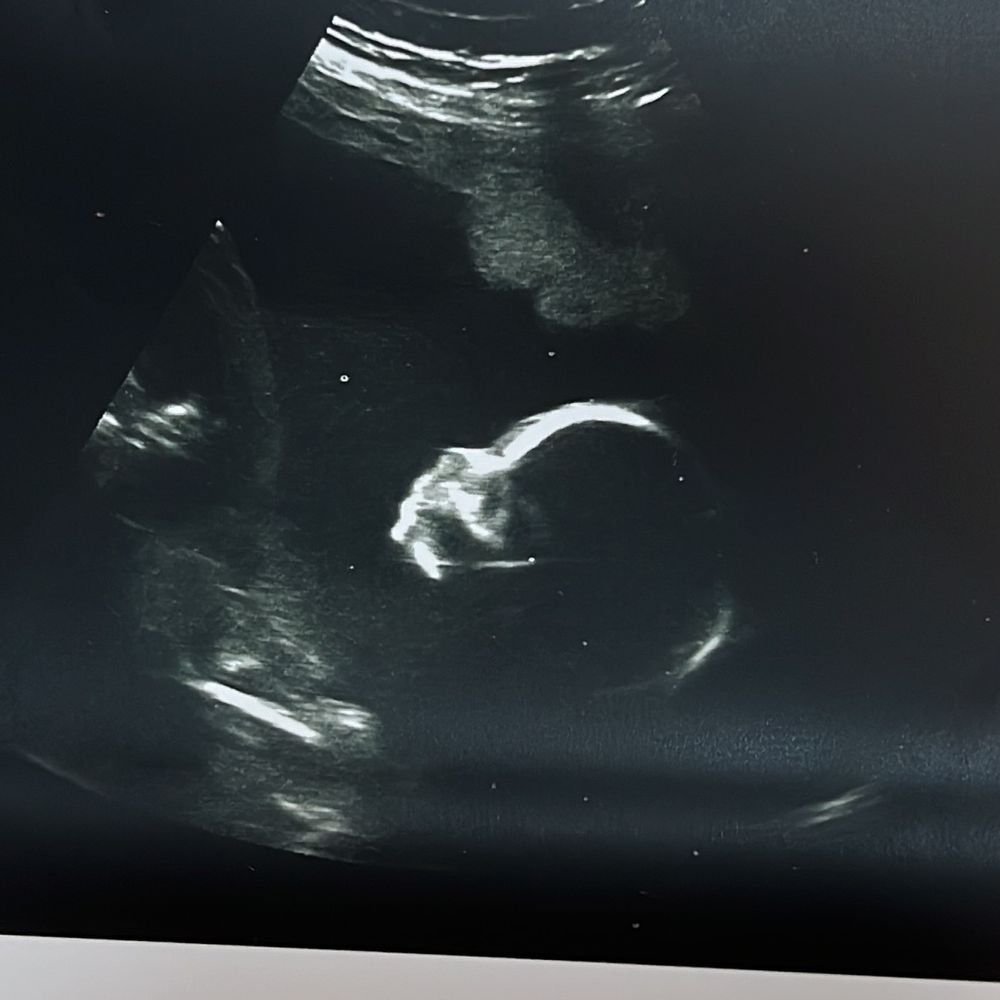

2 скрининг пройден 💕

УЗИ, КТГ, доплер

345 грамм счастья 🙈

Шевеления уже ощутимые, даже видно. Малышка постоянно закрывалась ручками и 3д сделать не получилось. Сын был не настолько скромным))

Сравнив результаты узи с сыночком, разница в показателях буквально 1 мм, только весил он у меня на этом сроке 353 гр))

Плацента поднялась, рубец хороший, шейку измеряли по животу-40, но в жк врач мерила вагинально (измерения проводит правильно ✅ , что очень нравится), 35 мм.